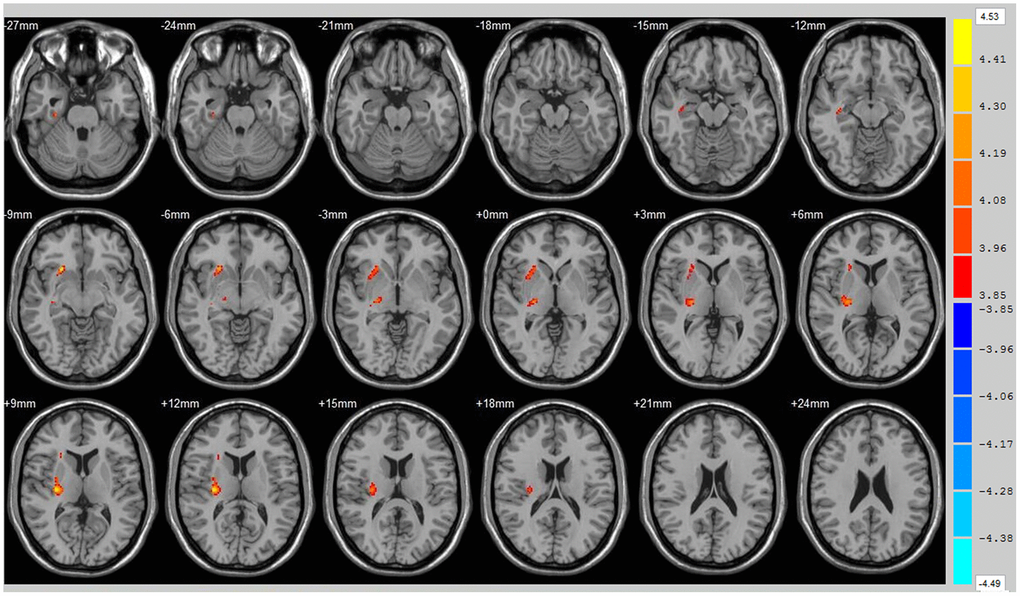

Using the whole brain analysis, we found that 1 week after ICH, patients displayed lower FA values in two brain clusters that included the ipsilateral temporal lobe, frontal lobe, insula, lenticular nucleus, putamen, caudate nucleus, hippocampus and thalamus than did the controls (Figure 1 and Supplementary Table 1). Two clusters with decreased FA values were also observed at week 12 (Figure 2 and Supplementary Table 2). Moreover, 12 weeks after ICH, six clusters (ipsilateral frontal lobe, lenticular nucleus, caudate nucleus, putamen, globus pallidus, and the contralateral parietal lobe, temporal lobe and hippocampus) exhibited higher FA (Figure 3, orange and Supplementary Table 3) while two clusters (ipsilateral limbic lobe, posterior cingulate gyrus and hippocampus) exhibited lower FA than at week 1 (Figure 3, blue and Supplementary Table 4).

Figure 1. Brain areas with decreased FA value at ICH patients at 1st w. Orange means the brain areas which FA value decreased compared with control group at1st w, Threshold=3.6594.